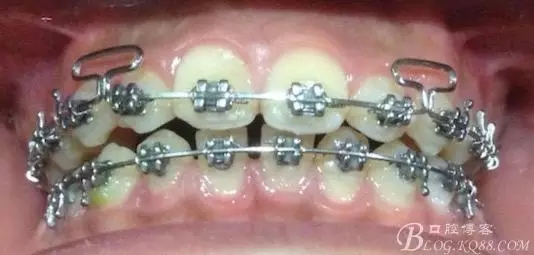

看看口內(nèi)照吧!真象“大暴牙”v假象“大暴牙”

三度深覆合,三度深覆蓋,尖牙,磨牙均二類關系!